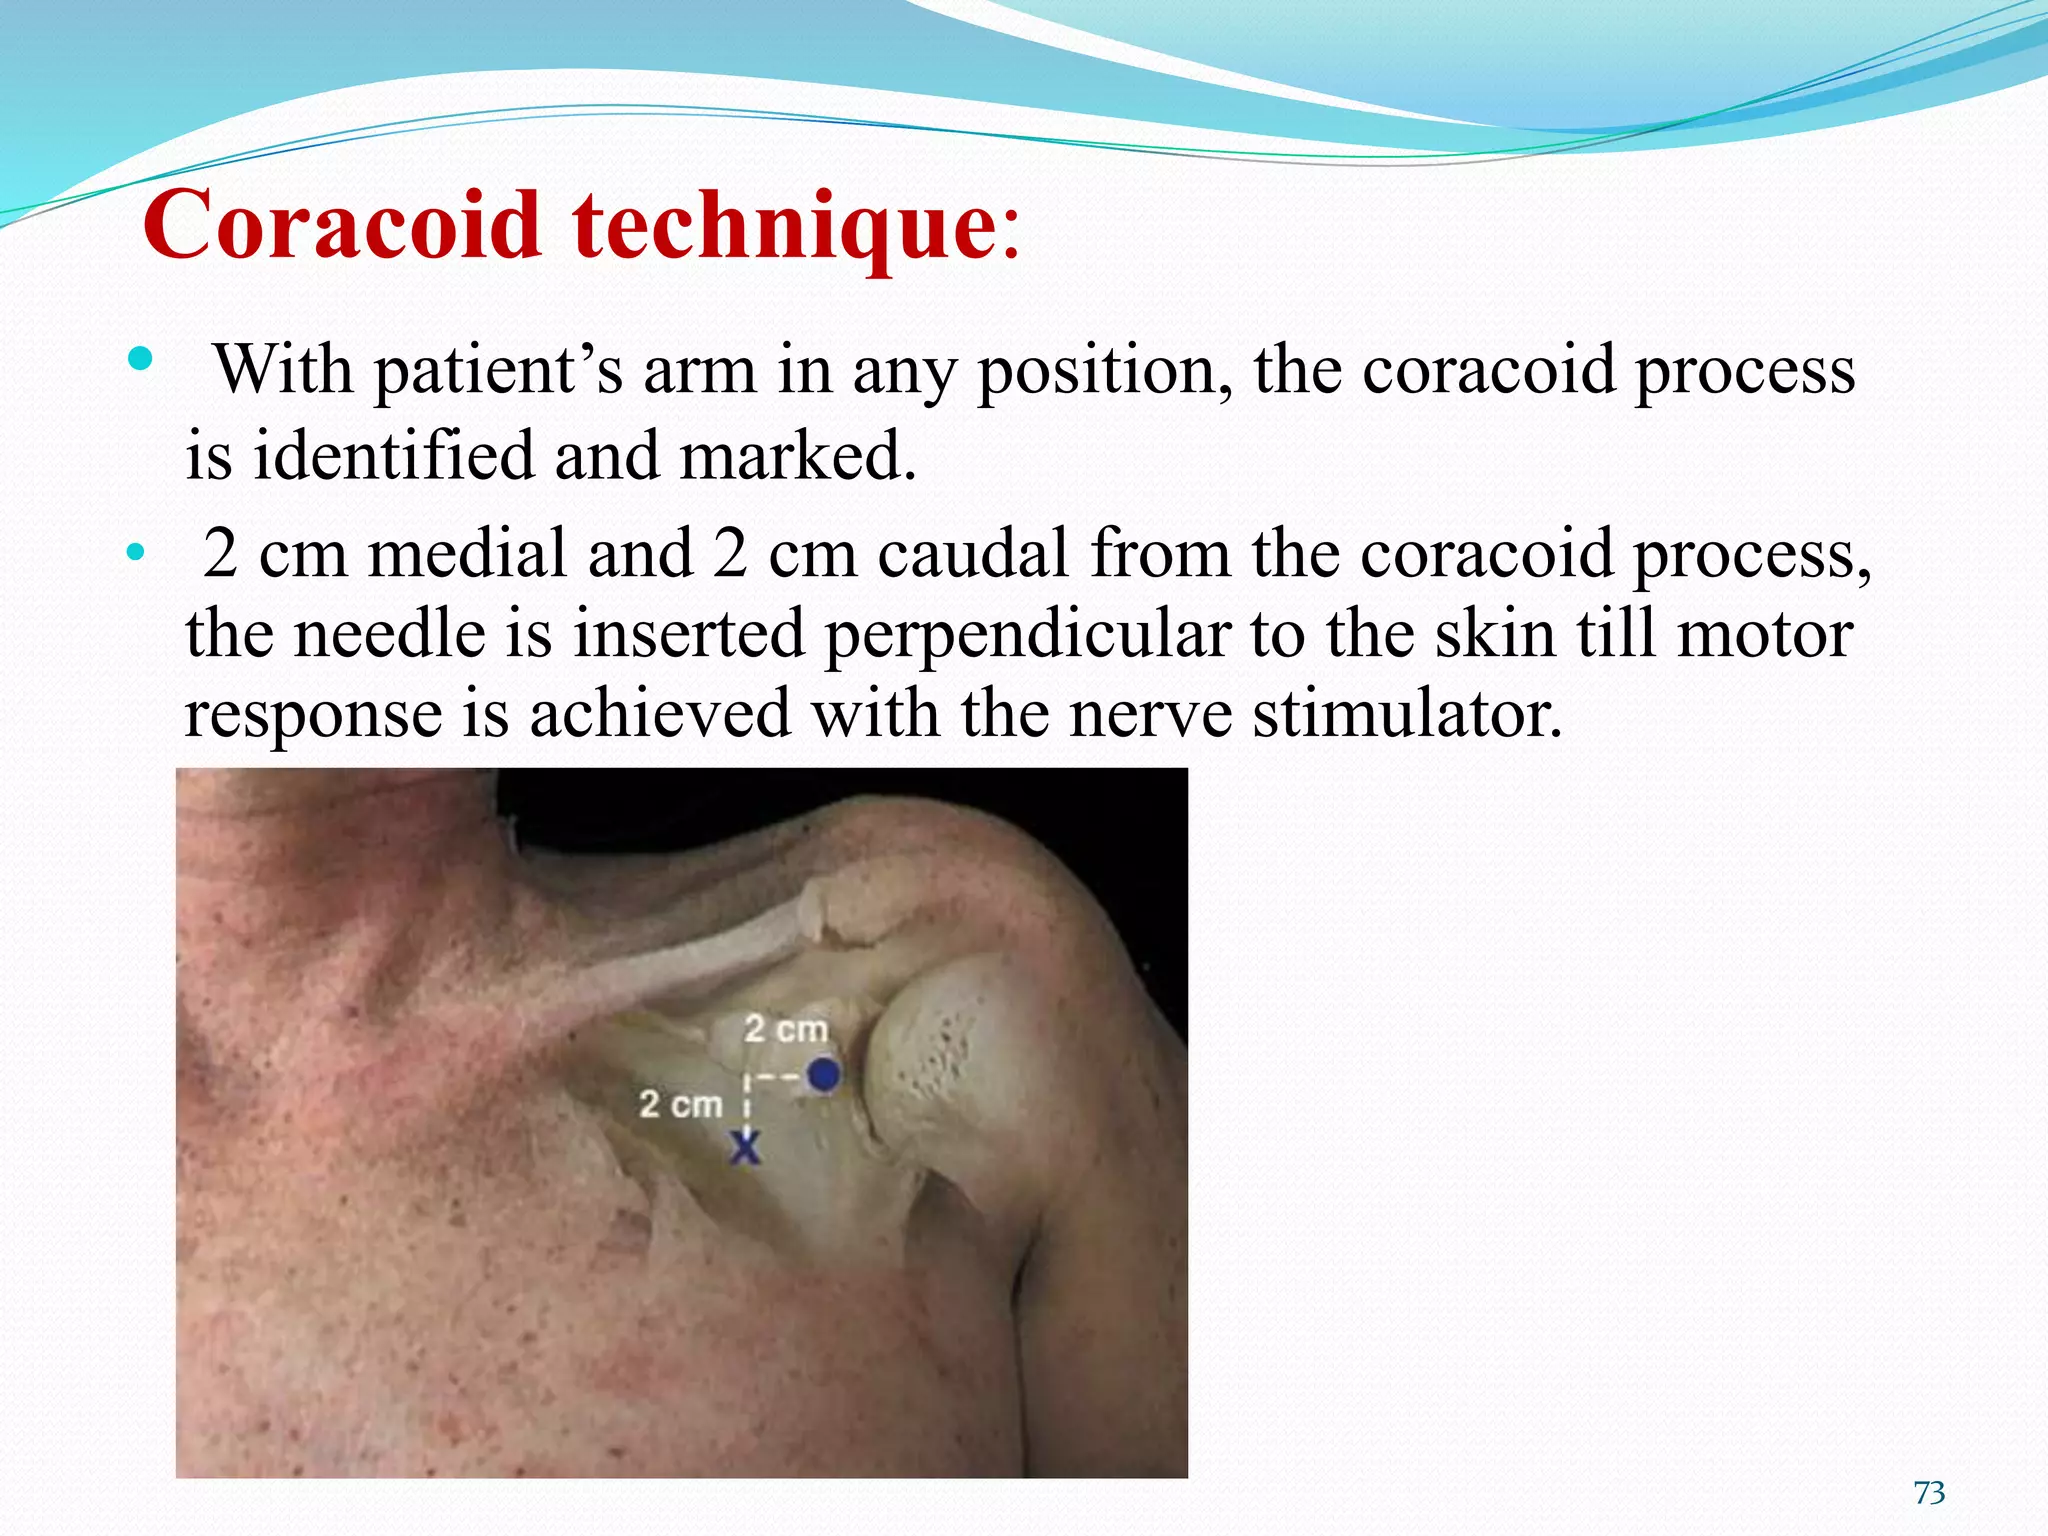

This document provides an overview of brachial plexus anatomy and techniques for brachial plexus nerve blocks. It begins with a description of the brachial plexus formation from cervical and thoracic nerve roots and its branching pattern. Four main approaches for brachial plexus nerve blocks are described: interscalene, supraclavicular, infraclavicular, and axillary. Details are provided on the anatomy and techniques for performing interscalene and supraclavicular brachial plexus blocks. Ultrasound guidance is discussed as an advancement which allows real-time visualization of needle and nerve. Complications are also summarized.